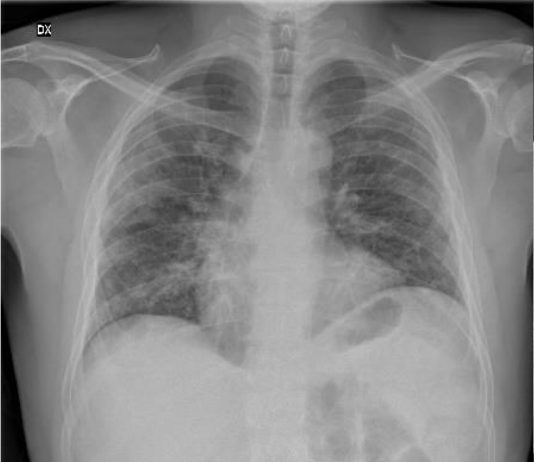

Femmina, 46 anni, non co-patologie, asintomatica. Si rileva saturazione pO2 98 % in aria ambiente. Riferisce dolori lombari aspecifici circa 10 giorni fa, risolti spontaneamente. In coabitazione con il marito (caso 14), che accompagna, senza...

Femmina, 61 anni, fumatrice. A novembre 2019 tosse febbre ed astenia trattata con Ceftriaxone, successivamente con Amoxicillina e terapia cortisonica. Da qualche giorno comparsa di tosse e febbre 37,8°, modesta astenia. Si rileva saturazione pO2 98...